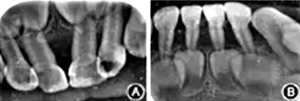

輔助檢查:基因檢測(cè)患者基因組ELANE基因有1個(gè)雜合突變(c.640G>A ),父母及其兄均未檢測(cè)到此突變,此突變?yōu)樽园l(fā)突變;血常規(guī):紅細(xì)胞3.13 × 1012/L,白細(xì)胞4.22 × 109/L,中性粒細(xì)胞絕對(duì)值0.48 × 109/L,血小板330×109/L,血紅蛋白83 g/L,C反應(yīng)蛋白>200 mg/L,超敏C反應(yīng)蛋白>5.0 mg/L。口腔X線片示牙槽骨呈廣泛性吸收達(dá)根中及牙尖1/3,遠(yuǎn)中切角缺損,牙冠可見低密度影像(圖2)。

圖2 重型先天性中性粒細(xì)胞缺乏癥患者前牙X線片示牙槽骨廣泛性吸收

A:上頜前牙;B:下頜前牙